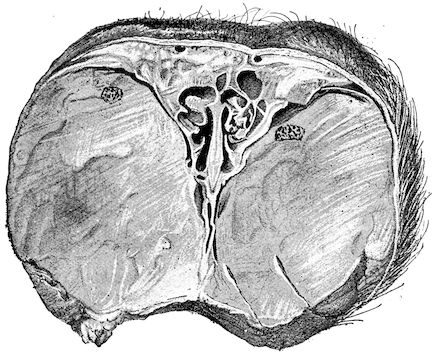

Fig. 8.—Transverse section through the middle region of the face in a pig suffering from osseous cachexia.

18In the final stages, the bones may be cut with a knife, and a time arrives when bony tissue seems completely to have disappeared; thus, as shown in Fig. 8 herewith, it was possible to cut the entire head of a pig into thin slices without the slightest difficulty. All parts of the head had been affected by the softening change.

From the chemical point of view, the diminution in mineral salts and in phosphate of calcium has long been recognised, but the degree of this change varies according to the phase. In human beings the proportions have been estimated as follows: Normal bone, 50 to 80 per cent. of phosphate of calcium; bone in persons suffering from osteomalacia, 5 to 20 per cent. of phosphate of calcium. The changes in the ossein have not been carefully studied. We only know that histologically the ossein becomes fibrillar, and that chemically it no longer retains its normal composition.